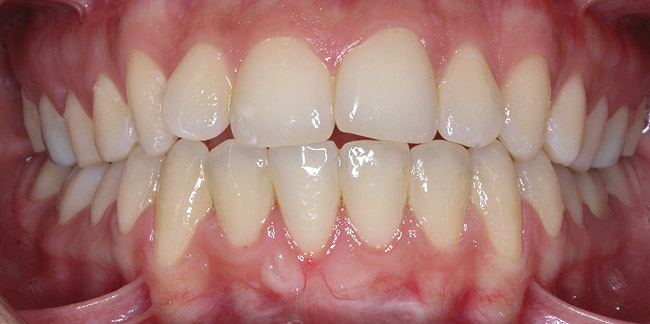

CASE 1 Fig 2. Pre-treatment clinical view of a 28-year-old patient with Miller Class I recession of the lower left central incisor treated with conservative SPT.

Figure 2

Fig 3. Two-year follow-up of same patient shows spontaneous root coverage.

Figure 3

When the tooth is properly aligned within the arch, treatment is managed with reference to Miller’s classification.7 Because most post-orthodontic GR cases are classified as Miller Class I and II defects, the authors focus on the management of these two classes only, and within the scope of this article, Miller Class III and IV defects are not addressed. Surgical root coverage of both Miller Class I and II defects is one treatment choice. However, in Miller Class I cases, a conservative approach can be considered, as well. Such an approach consists of supportive periodontal treatment (SPT)—professional periodic deposit removal every 2 to 3 months during a 1- to 2-year period. The authors’ clinical experience shows that spontaneous root coverage may occur following this conservative approach, particularly in young patients (Figure 2 and Figure 3). Similar results have been reported in a 3-year prospective study in which recession defects healed spontaneously following improvement in oral hygiene standards in children.30 In cases in which no root coverage is observed at the end of the follow-up period, surgical root coverage can be considered.